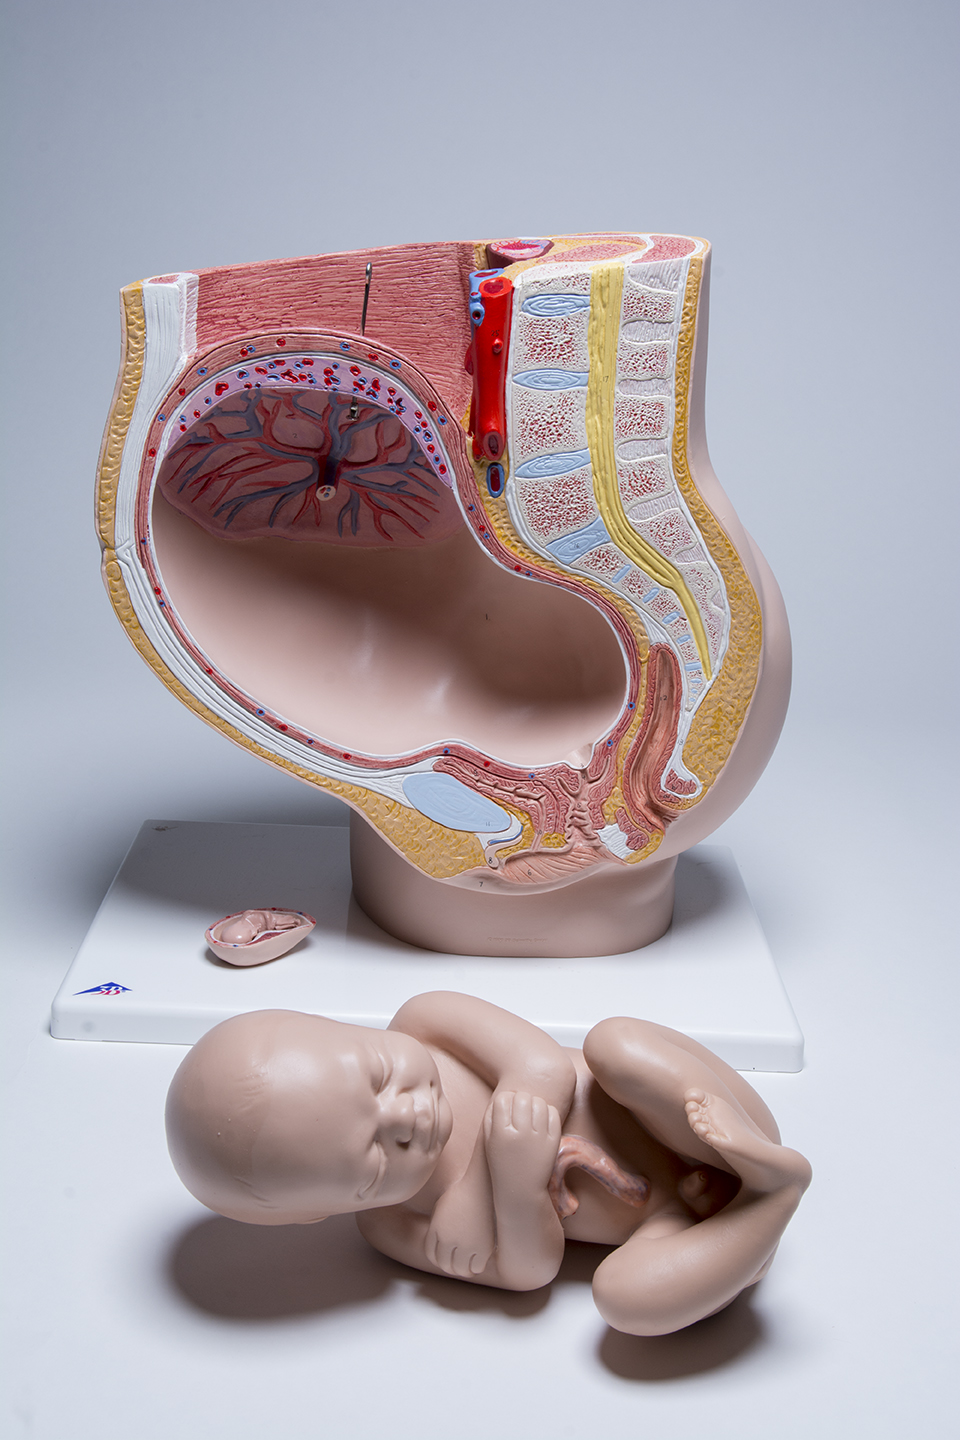

Pelvic Anatomy Pregnancy Model

This anatomy pregnancy model is a representation of a median section through the female pelvis at 40 weeks pregnant with a removable fetus. Study the normal position of child before birth with this model plus the human reproductive and urinary systems. A uterus with embryo in 3rd month of pregnancy is mounted on base for added detail. The realistic and high quality female pelvis includes the female genital organs and other important anatomical details. This pregnancy female pelvis is a great addition to any anatomy classroom or clinician’s office to educate about the effects of pregnancy.

This pelvic anatomy pregnancy model allows the clinician to easily explain what is taking place internally during pregnancy and how it affects surrounding organs, muscle and bone. This will enable to clinician to point out the many issues that can arise from childbirth and what can be done proactively to prevent them.